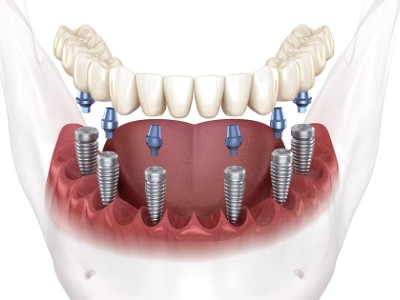

임플란트는 쉽게 말씀드리면 치아를 제거한 부위에 인공적으로 만든 치아를 즉, 임플란트를 식립 하는 시술입니다.

치과임플란트 급여안내 목적 건강보험 보장성 강화의 일환으로 노인의 저작기능 개선을 통한 건강증진 및 삶의 질 향상을 도모하기 위함 치과임플란트란? 치아가 빠진 경우 인공치아를 심어서